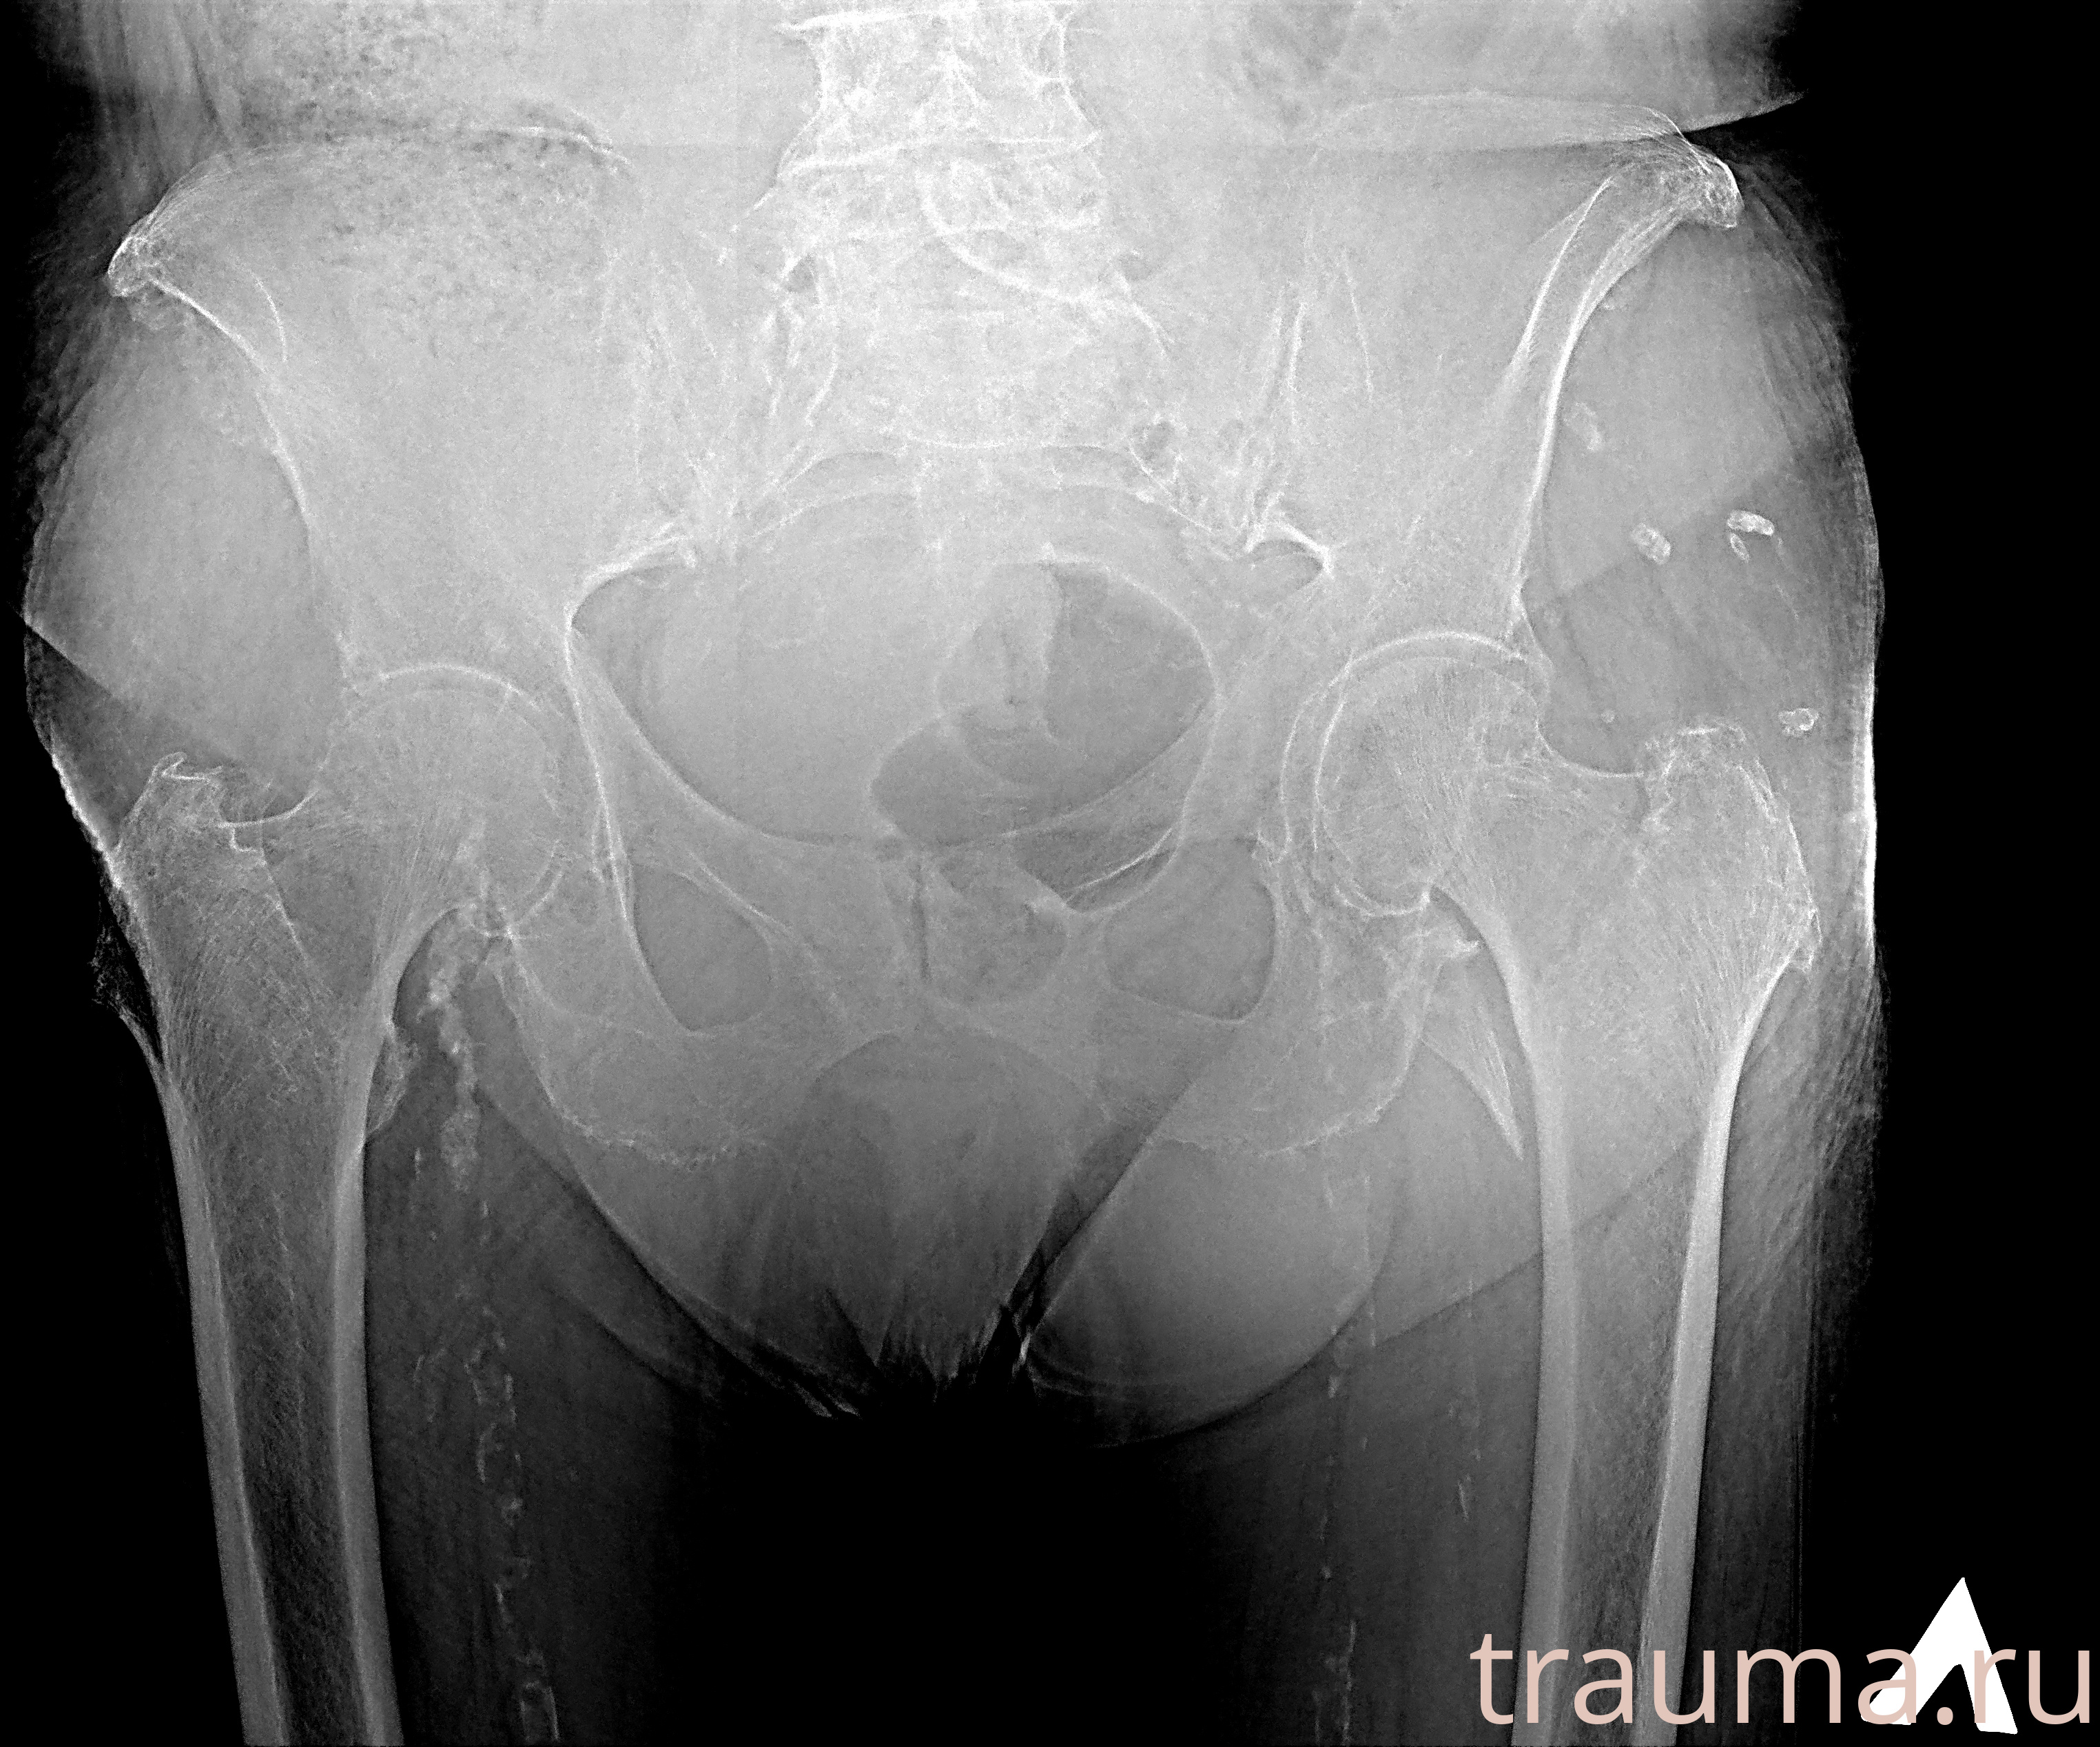

Рентгенограммы

Рентген на дому: по вашему адресу приезжает врач-рентгенолог, травматолог-ортопед с мобильным рентгеновским аппаратом, проводит диагностику травмы или заболевания, делает необходимые рентгенограммы, дает рекомендации по дальнейшему лечению. Получить качественные снимки в домашних условиях возможно благодаря уникальной методике, разработанной МосРентген Центром для института  Склифосовского

Яркость: 1   Контраст: 1   Инвертировать: 0 Увеличение: 1

Перетаскивайте мышь вверх/вниз для контраста, влево/право для яркости. Прокрутка колесом изменяет масштаб. Нажмите Сбросить для возврата к исходному изображению. При увеличении держите мышь в той области, которую хотите рассмотреть.